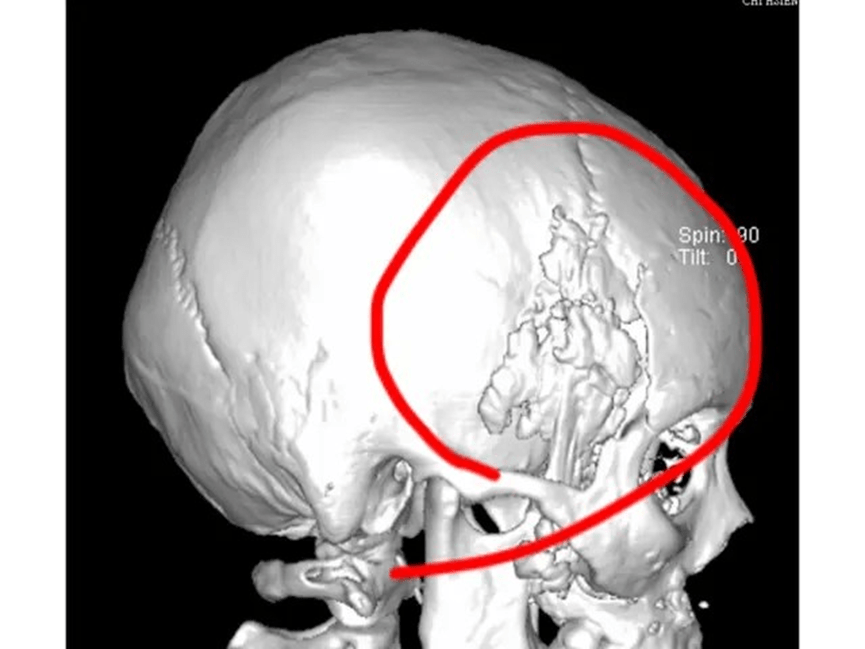

1. 注射填充——如玻尿酸或其他人工填充劑,但因為咀嚼肌的活動,這些材料會比其他部位更快吸水膨脹和變形及移位,容易造成不平整。可能出現凹凸、吸收、移位往往需要一再修補觸逐漸的饅化與走形。下圖3D電腦斷層掃描可見填充劑在組織纖維間隙的堆疊。凹凸不平是合理的,修補容易逐漸饅化。

下圖: 3D電腦斷層掃描下發現填充注射後的材料不平均的堆疊

電腦斷層發現:下圖為墊片位置穩定平順(紅色箭頭),下下圖紅圈處為注射脂肪下移與吸收不均的腫塊。為李醫師客製化墊片手術後兩年半長期和太陽穴注射填充結果比較:

Filler/ fat augmentation is quite different from the implant sheet on temple area. Long term results show on 3D CT scan, we can find the filled temple disfigured a lot compared with the implant sheet on temple contour.

上圖:在3D電腦斷層掃描顯像:微創墊片在太陽穴(近三年)和注射填充的效果對比